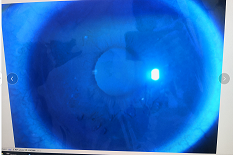

圓錐角膜要做那種治療比較好

【文章導(dǎo)讀】圓錐角膜的治療應(yīng)該依據(jù)角膜發(fā)展的時(shí)期選擇。目前圓錐角膜按照臨床癥狀大致可以分為四個(gè)時(shí)期,分別為潛伏期、初發(fā)期、完成期和瘢痕期,各個(gè)時(shí)期的主要癥狀表現(xiàn)如下: 潛伏期:

圓錐角膜的治療應(yīng)該依據(jù)角膜發(fā)展的時(shí)期選擇。目前圓錐角膜按照臨床癥狀大致可以分為四個(gè)時(shí)期,分別為潛伏期、初發(fā)期、完成期和瘢痕期,各個(gè)時(shí)期的主要癥狀表現(xiàn)如下:

完成期:發(fā)展迅速,角膜明顯前突,視力銳減。

瘢痕期:角膜急性角膜水腫、混濁,消退后基質(zhì)層殘留瘢痕。

圓錐角膜的形成機(jī)制就是膠原變薄,變?nèi)?。圓錐角膜患者的角膜膠原變薄了以后,彈性增加,正常的眼壓會(huì)使角膜向前膨隆。

角膜膠原交聯(lián)手術(shù)可以通過(guò)藥物,維生素B2和紫外線交聯(lián),使角膜里面的膠原纖維的硬度增加,在對(duì)抗正常眼壓情況下,對(duì)抗力增加。交聯(lián)后角膜的韌度增加,就不容易再往前繼續(xù)發(fā)展。

但如果已經(jīng)發(fā)展到圓錐后期,再去交聯(lián)就沒(méi)有意義,就只能通過(guò)角膜移植手術(shù)治療,把向前凸起的角膜給切掉,換成新的角膜。

目前圓錐角膜的治療方式主要就是配鏡矯正、角膜膠原交聯(lián)手術(shù)以及角膜移植手術(shù)這幾種。